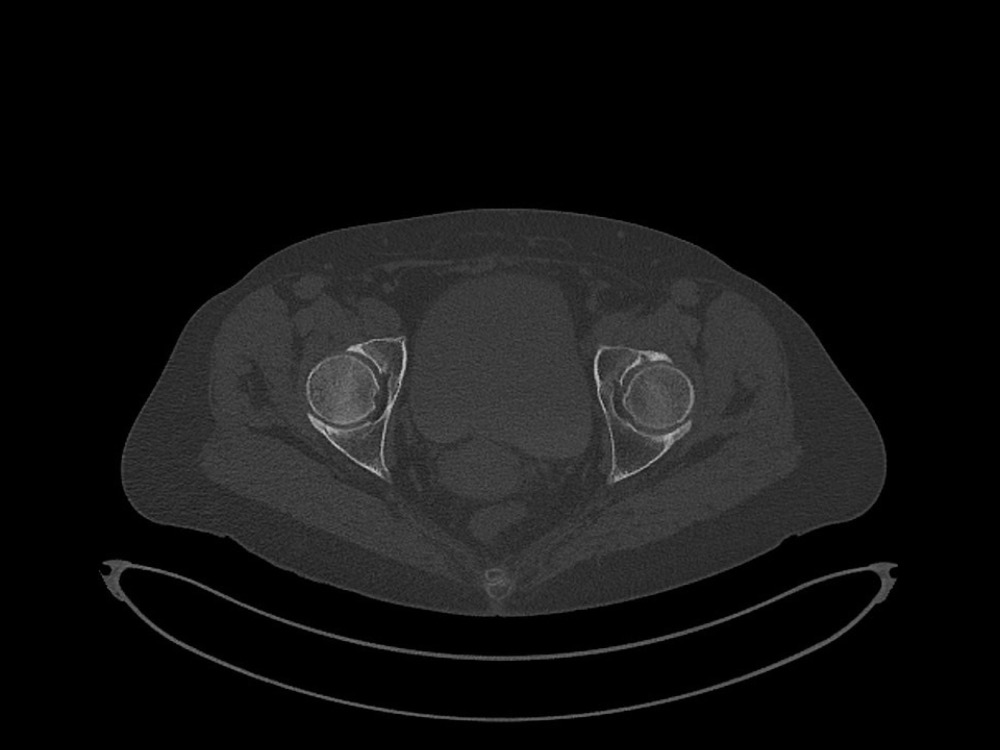

Douleurs de hanche

Linda Ouerd 06/11/2019